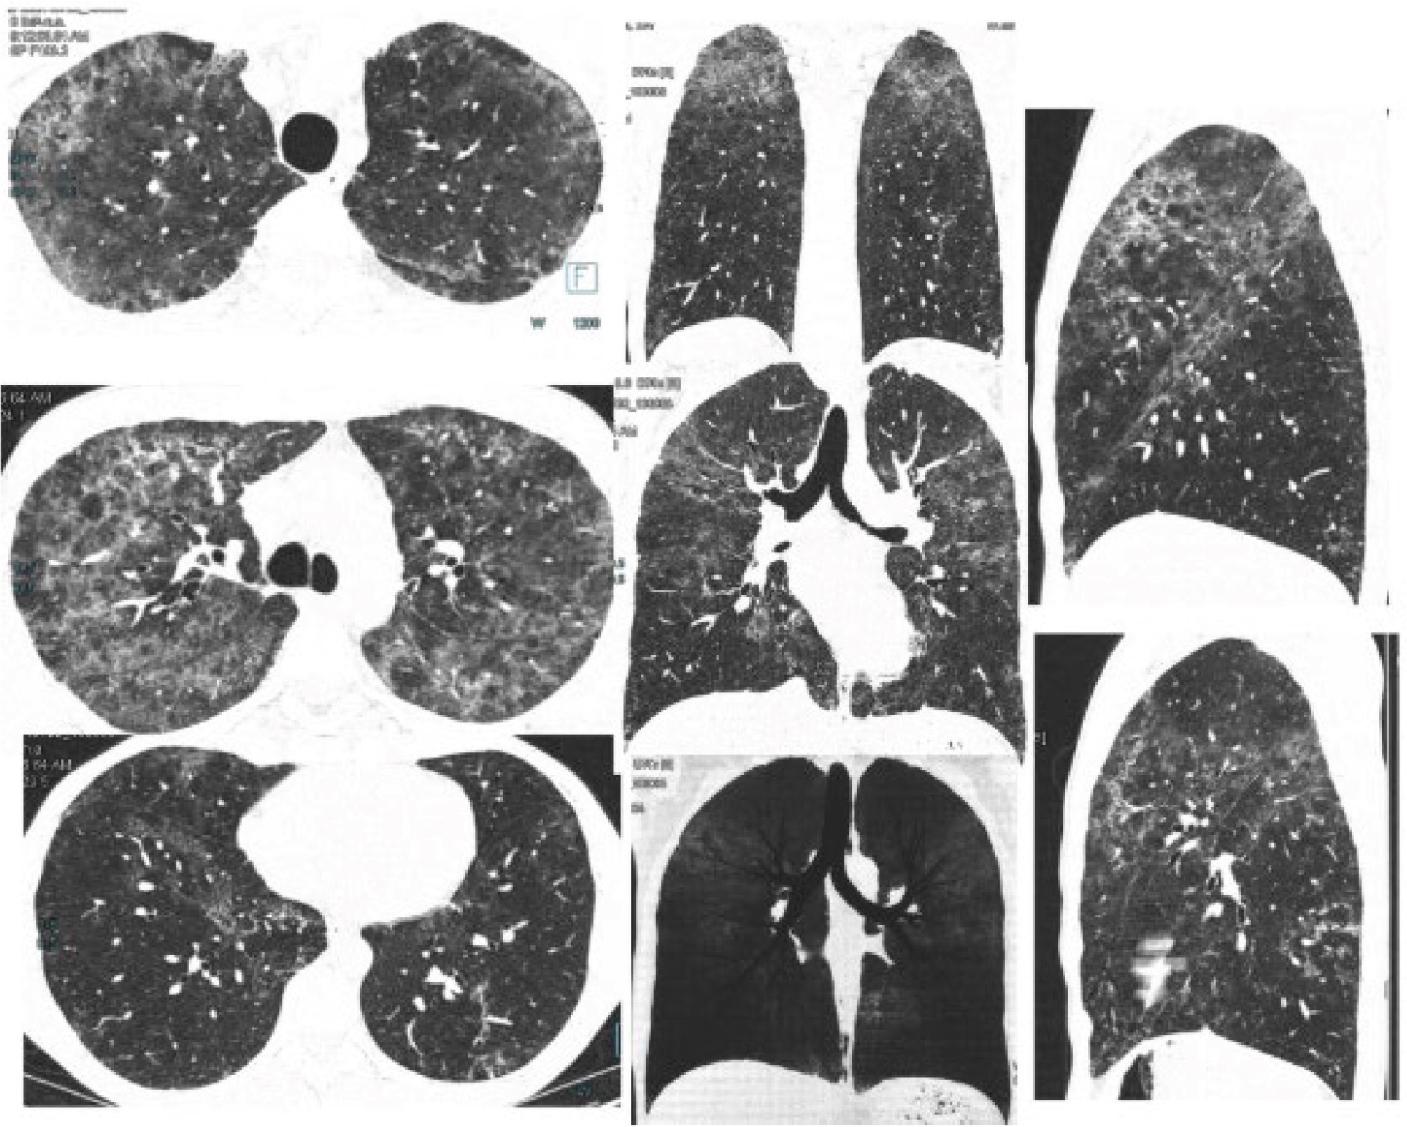

Two days later, the patient returned with recurrent fever and shortness of breath. On examination, his oxygen saturation was 89%, his heart rate was 123 bpm and he appeared mildly lethargic. He was re-admitted and treated with intravenous antibiotics (levofloxacin 500 mg once daily and cefotaxime 1 g three times daily) for 7 days. He was then discharged and referred for a pulmonology outpatient visit, where he presented a month and a half later with persistent dyspnoea (modified Medical Research Council grade 2) and unintentional weight loss. A chest X-ray revealed an interstitial pattern (Figure 2), prompting a repeat CT scan performed in August 2024, approximately 3 months after the initial CT examination, which demonstrated a diffuse interstitial pneumonia pattern, with patchy ground-glass opacities in a mixed central (peribronchovascular) and peripheral distribution, with subpleural sparing. Lesions were predominantly distributed in the upper lobes. The consolidations in the lower lobes had resolved (Figure 3).

Transverse, coronal (MPR and MinIP) and sagittal high-resolution CT performed 3 months after the initial episode of dyspnoea showing subpleural and central ground-glass opacities in both lungs, predominantly in the upper lobes, with septal thickening, intralobular lines and distortion without microcysts (pattern suggests NSIP). Consolidations of the lower lobes have disappeared. CT, computed tomography; NSIP, non-specific interstitial pneumonia.